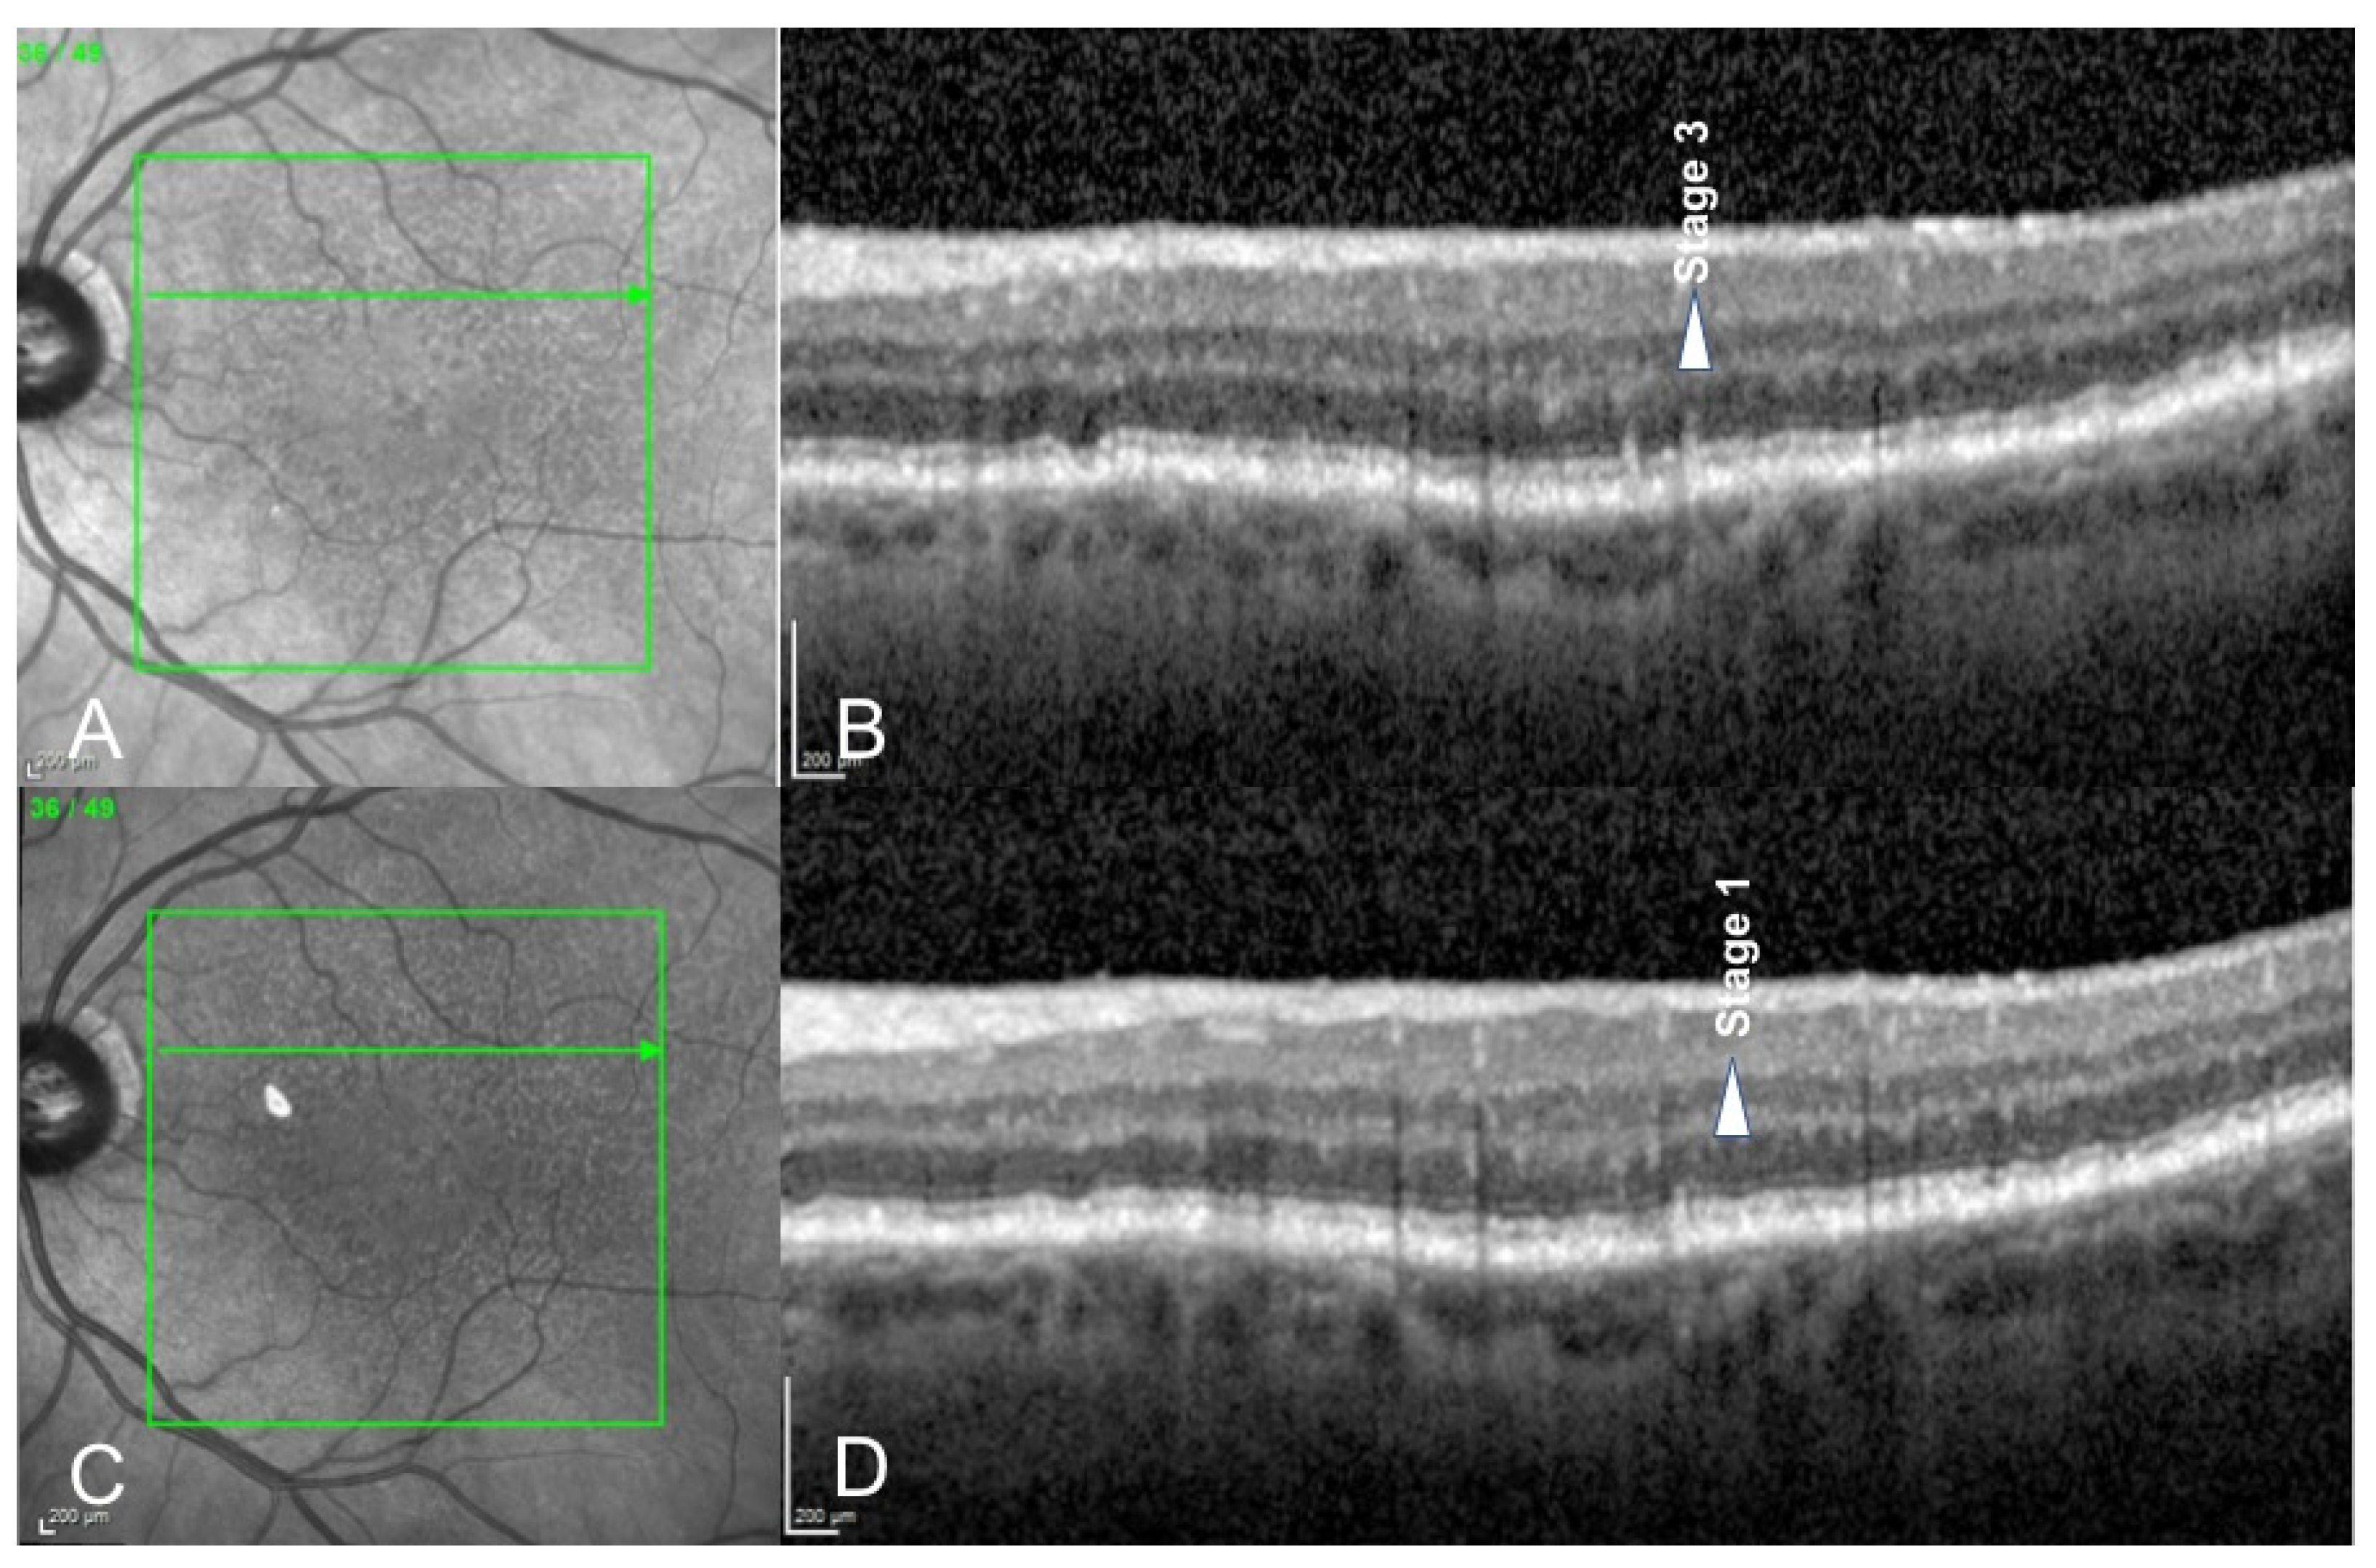

3. Results